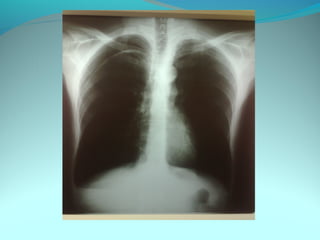

Opacité occupant la partie externe du 1/3 infer du poumon droit

dense et homogene ovalaire de 8cm de grand axe vertical

La limite externe se confend avec une opacité d’environ 1cm comble

les coupole costodiaphragmatique droit

Limitée a sa partie sup par la petit sessure qui est epaisse et pas de

lyse costale

 DIAGNOSTIC :DIAGNOSTIC :

 1_1_cancer bronchique droit( d epaississement)

 2_2_ kyste hydatique au stade sain